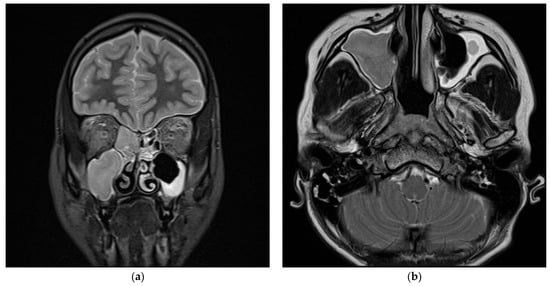

2.2. Case Two—Pansinusitis, Bilateral Otomastoiditis, and Parapharyngeal Abscess Complicated by Acute Mediastinitis, Thrombophlebitis, and Vein Thrombosis

2.2.2. Initial Assessment and Hematological and Radiological Investigations